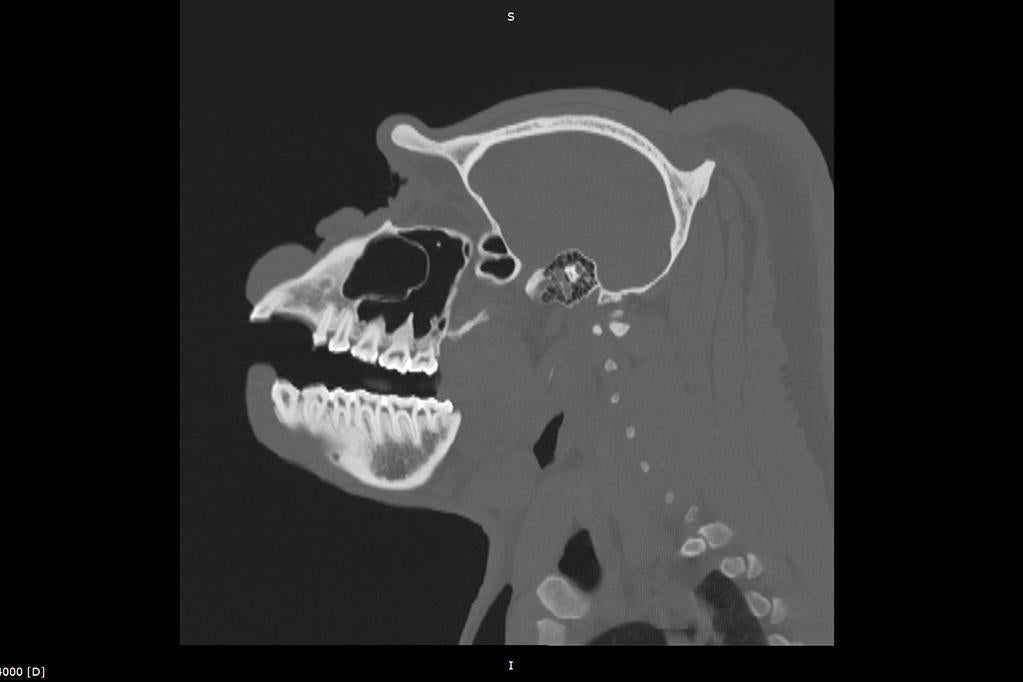

Much like your visits to the dentist, animals undergo everything from detailed tooth charting to advanced imaging such as X-rays or CT scans, helping identify problems before they could potentially become more serious conditions. Treatments can include cleanings, root canals, or extractions, providing each animal with care and support for their long-term health.

Similar to how some people are more prone to cavities, certain animals can be more prone to dental issues. But because of advanced diagnostics, we can detect and address these problems much earlier and improve outcomes significantly. In native habitats, wildlife with untreated dental issues often endure chronic discomfort or life-threatening complications. That’s why our veterinary teams take what they learn here at the Zoo and Safari Park and share it with our partners to save, protect, and care for wildlife worldwide through our eight Conservation Hubs.